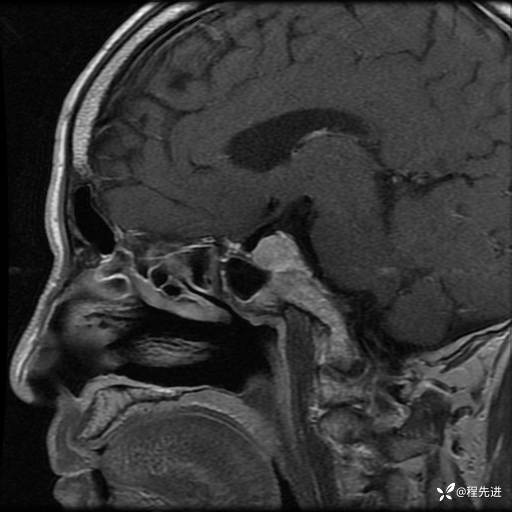

MRI平扫+增强:

T1:

T2: